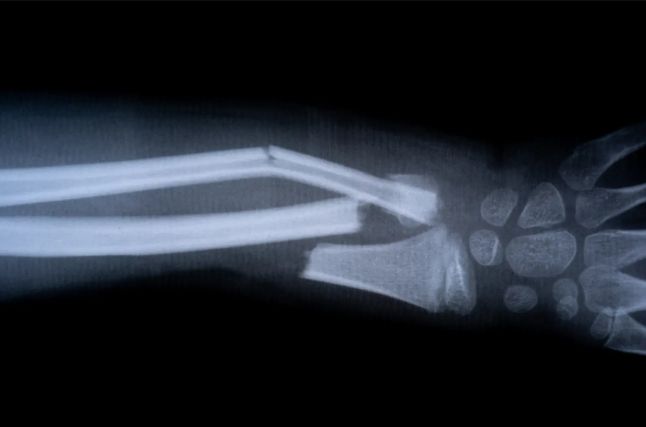

Çinli tədqiqatçılar sınıq sümük parçalarını 2-3 dəqiqəyə birləşdirə bilən dünyada ilk “sümük yapışqan” materialını təqdim ediblər. Bu yeni biomaterial sümük sağaldıqca altı ay ərzində əmilir.

Çin tədqiqat qrupu tərəfindən hazırlanmış "Sümük-02" adlı məhsul, adətən aylarla immobilizasiya və metal lövhələrin daxil edilməsini əhatə edən ortopedik zədələri sağaltmağı hədəfləyir.

Sümük-02 sümük yaxşılaşdıqca bədən tərəfindən təbii şəkildə sorula bilər və implantları çıxarmaq üçün ikinci əməliyyata ehtiyacı aradan qaldırır.